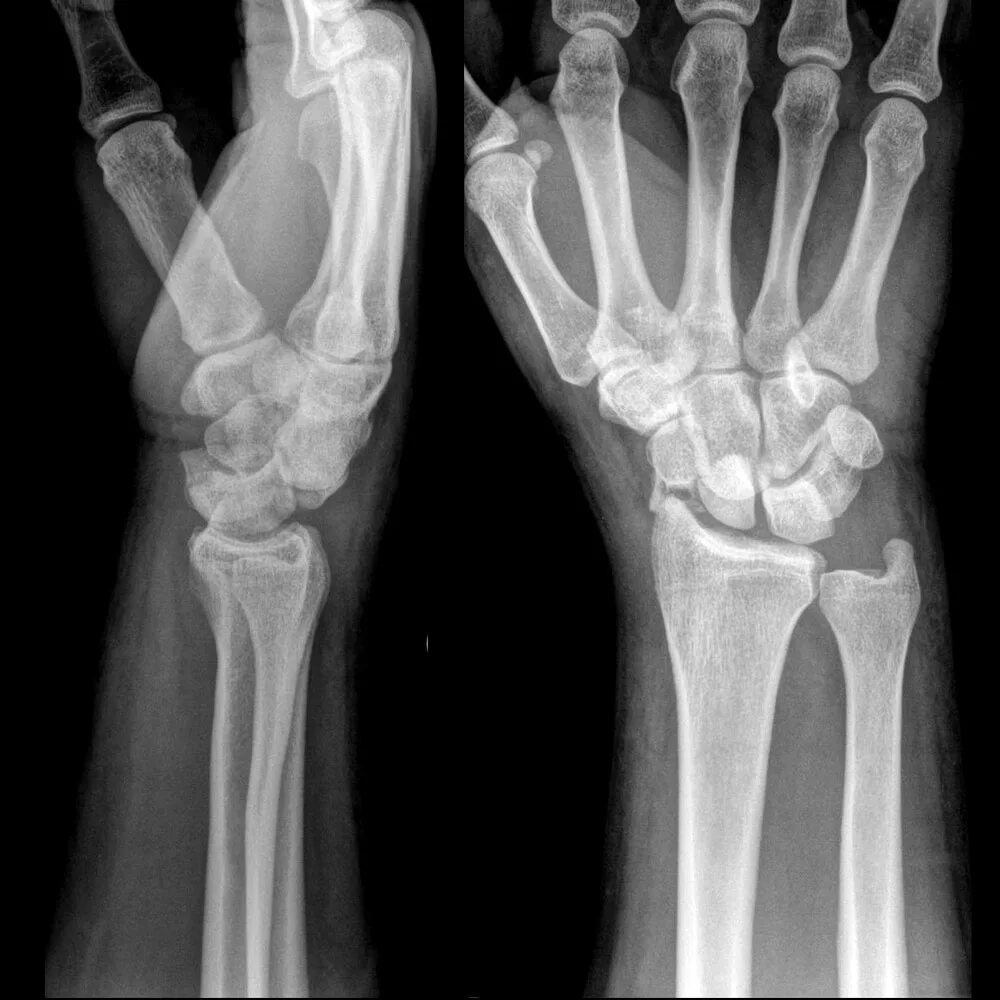

Вывихнутое запястье